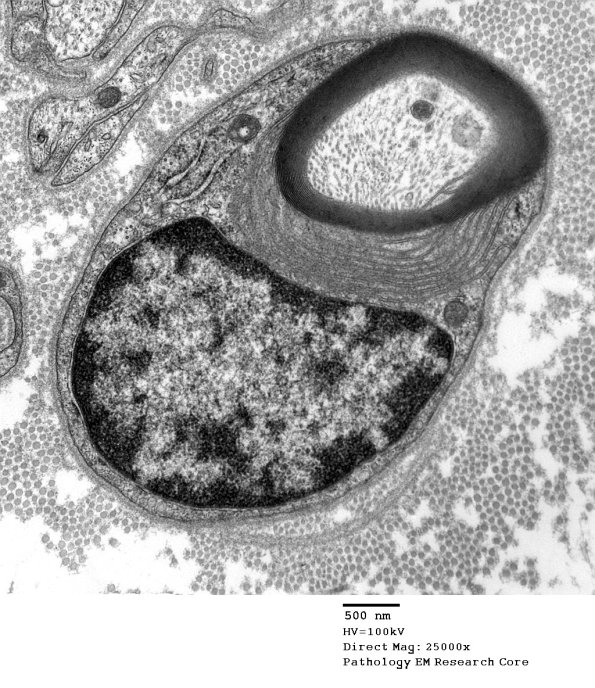

An example of uncompacted myelin from a case of POEMS syndrome. (electron micrograph)